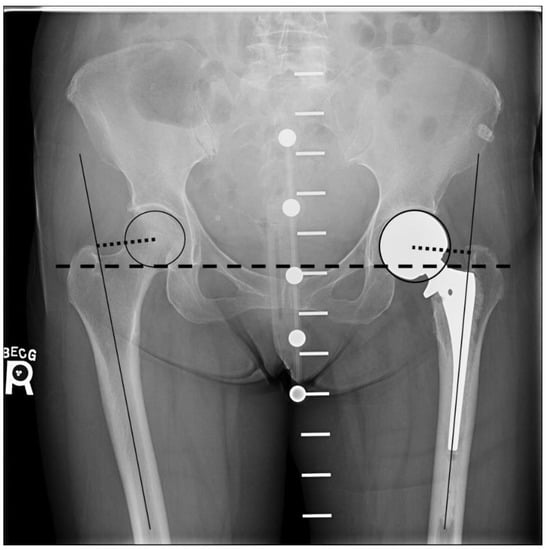

Measurements to calculate leg lengths and femoral offset were made using TraumaCad digital software (Brainlab AG, Munich, Germany). Postoperatively, a leg length discrepancy between the operated leg and the contralateral leg was determined by measuring the difference in the perpendicular distance from the inter-teardrop line to the superior aspect of the lesser trochanter of each hip [21,22] (Figure 1). Femoral offset of both hips was calculated as the distance from the center of the femoral head to a line bisecting the long axis of the femur (Figure 1). The center of the femoral head was identified by using the circle tool to match the femoral head diameter, which then provided the central point for the offset measurement. All measurements were performed by a single operator (AB) under the supervision of an arthroplasty surgeon (MT). The measurements were performed two times for each radiograph, and the means were used to compare the operated and non-operative control side within each group. Any difference in the leg length or femoral offset of 2 mm or more was considered as significant, while any difference of 5 mm or more was considered excessive since it results in un-physiological gait kinematics after hip arthroplasty [23].

Figure 1. Postoperative AP radiograph of the pelvis with the pelvic calibration device demonstrating a left cemented hemiarthroplasty. The dotted line from the center of the femoral head to the line bisecting the long axis of the femur is the femoral offset. Length discrepancy is determined by measuring the difference in the perpendicular distance from the inter-teardrop line (dashed line) to the superior aspect of the lesser trochanter of each hip.